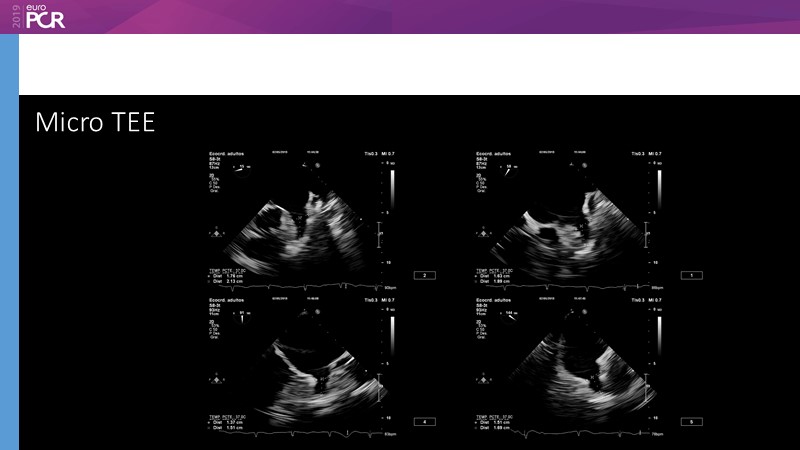

Pre-procedure planning

Previous Next